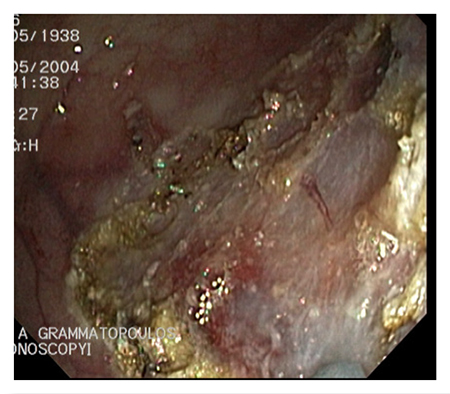

Endoscopic Removal Of Large Sessile Polyps And Submucosal Lesions

A sessile polyp is any flat wall growth without a stalk, usually detected during an endoscopic exam.

Sessile polyps differ in size, ranging from a few milliliters to several centimeters, and may be located anywhere along the digestive tract.

Submucosal lesions are tumors – usually benign, but also malignant in some cases – that are located inside the digestive tract wall. In the majority of cases they are covered by normal mucosa. When the endoscopy specialist detects a sessile polyp or a submucosal lesion, the first thing they consider is how to remove it completely, without causing any complications or prompting any future relapse. The most difficult to manage polyps are the ones located in the second part of the stomach duodenum, as well as the adenomas of the ampulla of Vater.

Our Hospital meets all these conditions. As a result, the endoscopic procedures are completely safe. Sessile polyps that are over 1 cm in size require special endoscopic management during polypectomy. A necessary condition is the submucosal injection of normal saline solution, with or without epinephrine, along with blue de methylene or indigo carmine. The infusion helps separate the mucosa and submucosa from the muscular layer. This technique also offers the endoscopy specialist the chance to understand whether they can remove the lesion. When the base of the polyp rises smoothly and easily, then it is possible to remove the polyp. The infusion may reduce the risk of bleeding and perforation following polypectomy.

Polyps that are over 2 cm in size may be removed in fragments or using the endoscopic submucosal dissection (ESD) method. Submucosal lesions are removed using a different procedure. Initially, the mucosa is lanced using a special lancet and the lesion is exposed. It is then separated from the surrounding tissue and removed.